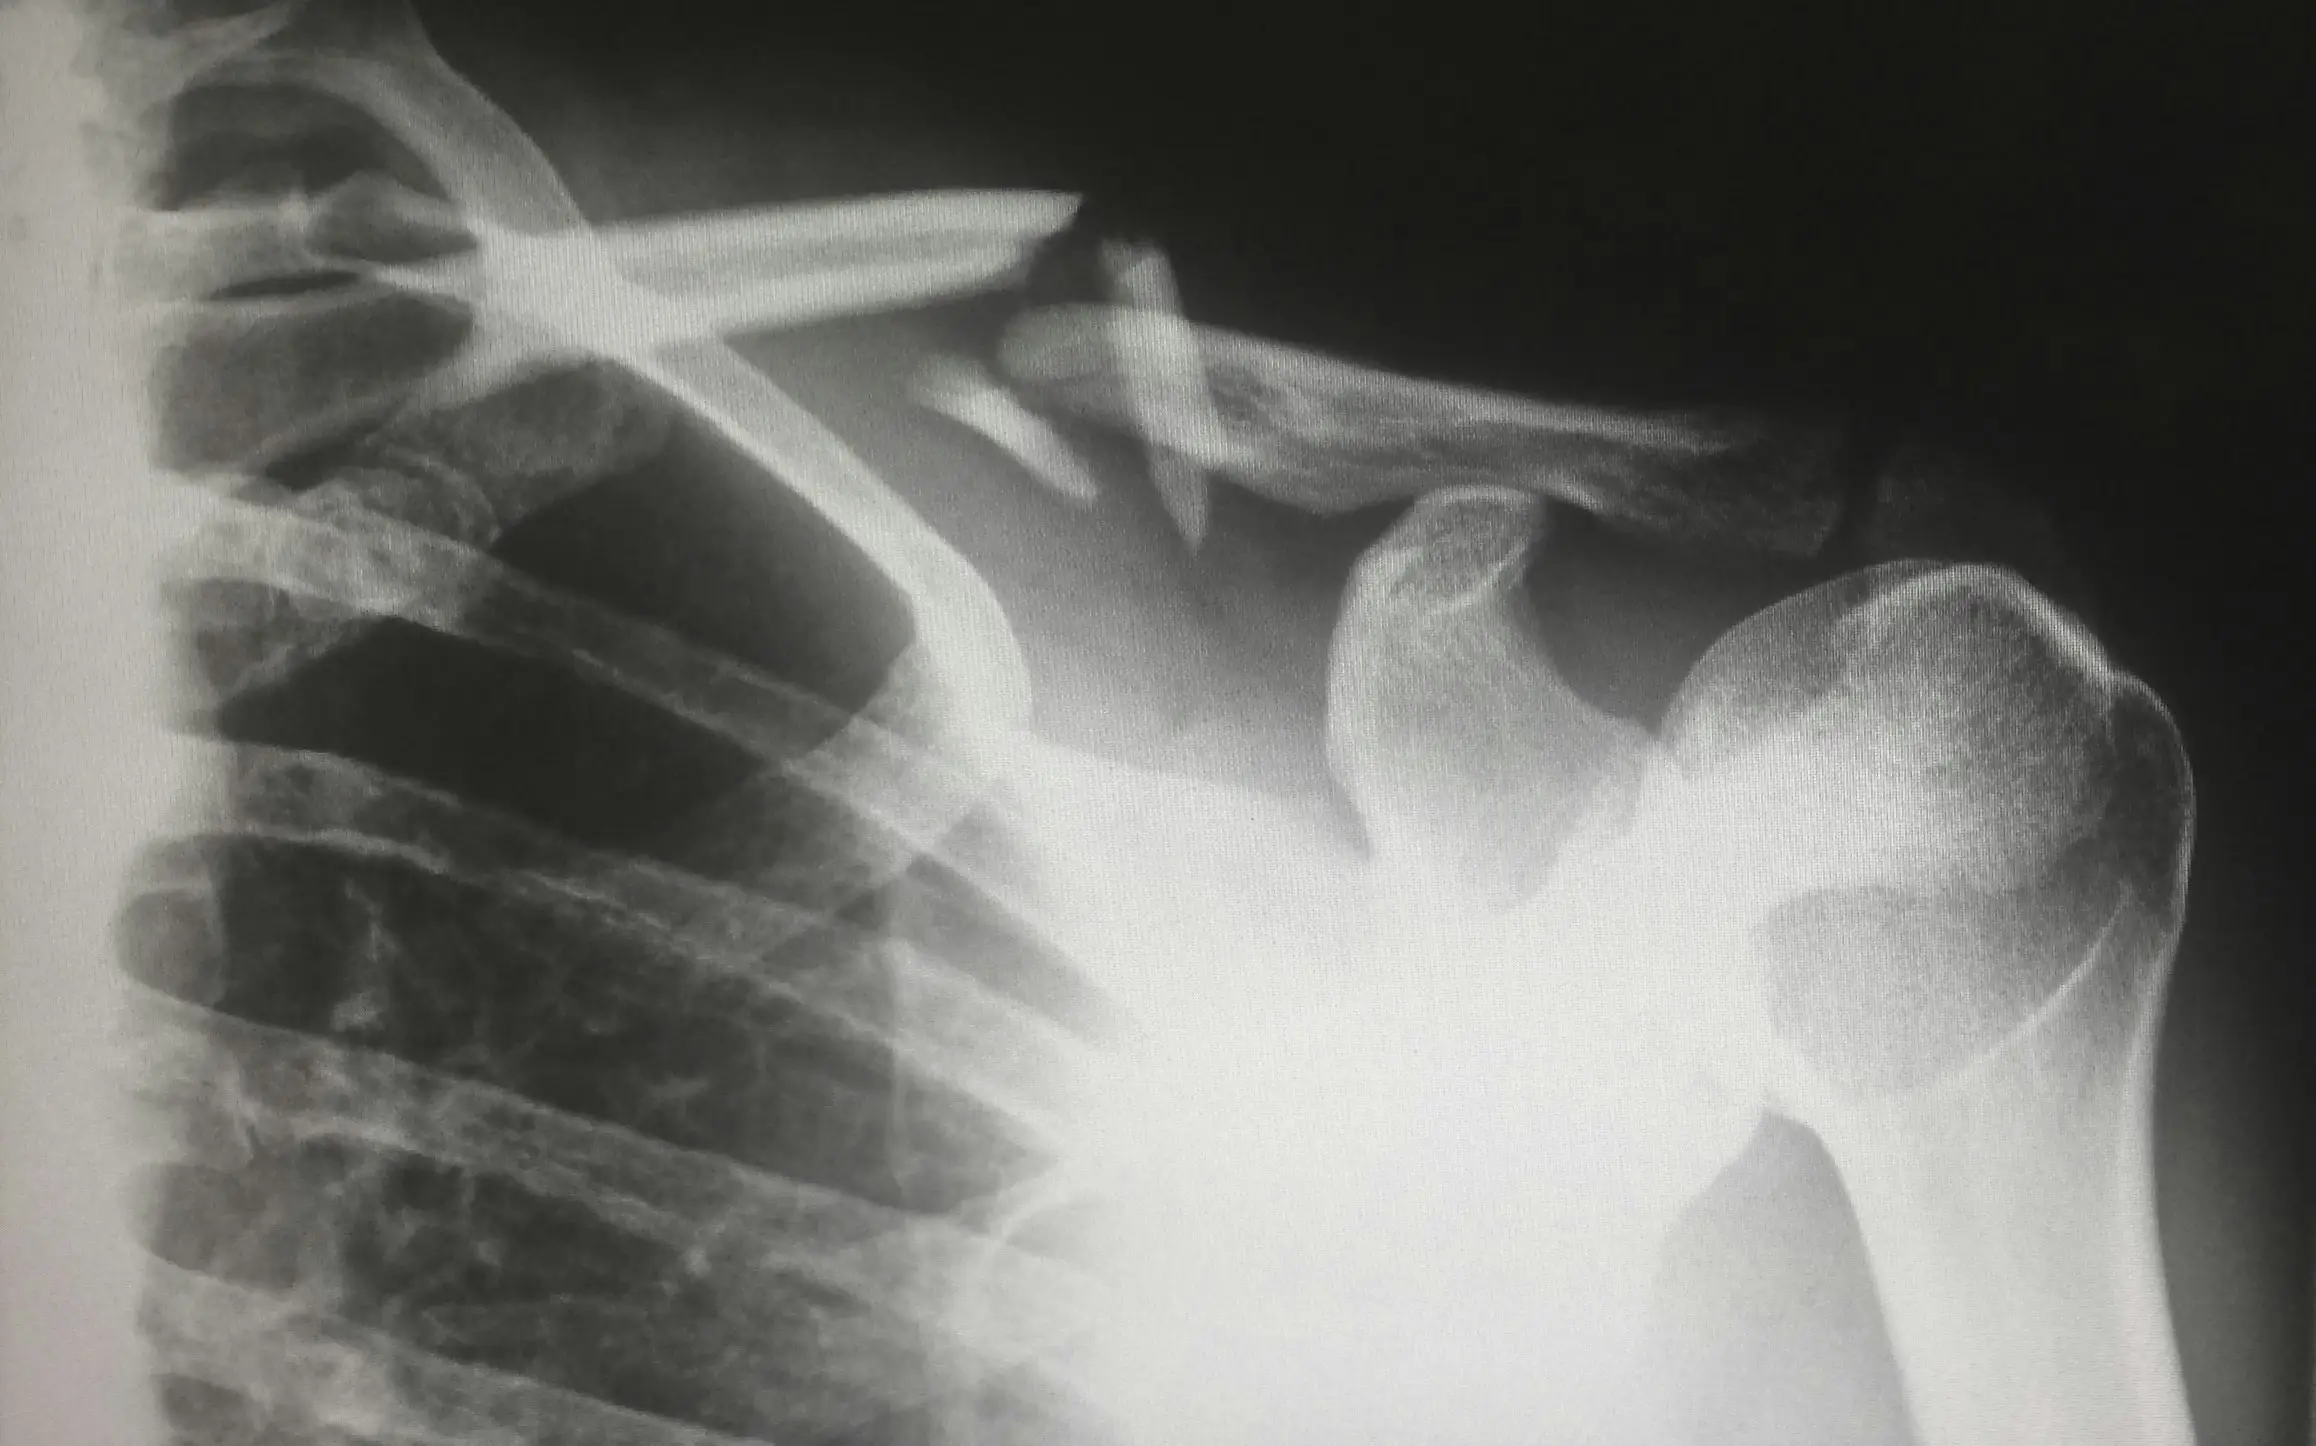

- X-ray, MRI, CT 등 영상 자료로 확인 가능할 것

- MRI·X-ray 등 영상자료 필수

- MRI, CT, X-ray 등 영상자료